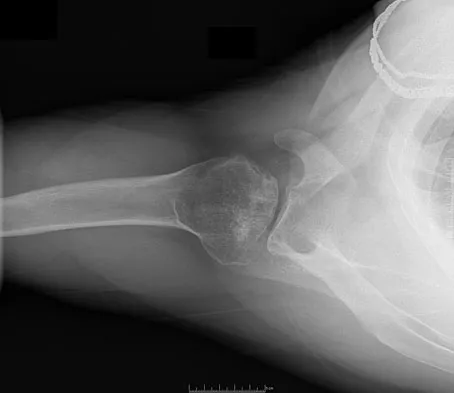

Figures 12a and 12b show the radiographs of a 50-year-old patient who reports acute knee pain after sustaining a twisting injury while playing tennis. Examination is unremarkable. The next most appropriate step in management should consist of

Explanation

The radiographs show localized diffuse cortical thickening that is characteristic of melorheostosis. The condition may be monostotic or it may involve many bones in one extremity (monomelic) in the distribution of a sclerotome. Bone scans will show increased uptake at the site or sites of skeletal involvement. Long tubular bones are most commonly involved. Melorheostosis is usually asymptomatic and requires no treatment. On rare occasions, there may be associated soft-tissue contractures. Dorfman H, Czerniak B: Bone Tumors. St Louis, MO, Mosby Inc, 1998, pp 1105-1107. Campbell CJ, Papademetriou T, Bonfiglio M: Melorheostosis: A report of the clinical, roentgenographic, and pathological findings in fourteen cases. J Bone Joint Surg Am 1968;50:1281-1304.